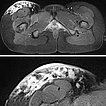

In der transversalen T2-Wichtung, fettunterdrückt, ist die rein epifasziale Ausdehnung der LM im subkutanen Fettgewebe klar zu erkennen. Die darunter liegende Muskulatur ist nicht betroffen.

Beachte in der Ausschnittsvergrößerung (unteres Bild) die exophytische Ausdehnung der mikrozystischen Anteile (stark hyperintens) der LM bis über das Niveau der Haut.

In der gleichen Schichtführung der MRT (oben Übersicht, unten Ausschnittsvergrößerung) in T2-Wichtung ohne Fettunterdrückung sind die gleichzeitig vorhandenen bindegewebigen Anteile der hart tastbaren LM als hypointense netzartige Zeichnung besser zu sehen. Beachte wieder den erhabenen exophytischen Anteil oberhalb des Hautniveaus.

In der axialen fettunterdrückten T1-Wichtung nach KM-Gabe (oben Übersicht, unten Ausschnitt) findet sich die stärkste Anreicherung in den kutan gelegenen, expophytischen, mikrozystischen Anteilen in der Haut. Die darunter liegende LM im subkutanen Fettgewebe reichert dagegen kaum an.